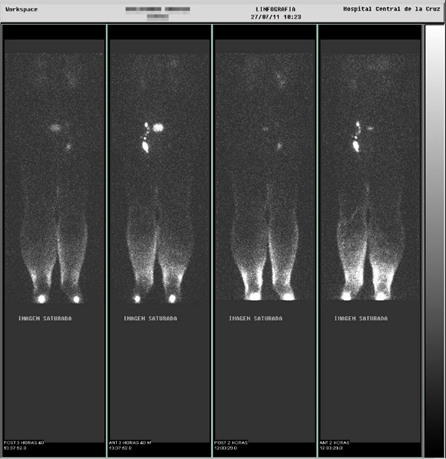

El linfedema o acumulo de linfa en los brazos o piernas tras un tratamiento por cáncer o sin una causa aparente,es una patología compleja que requiere un abordaje interdisciplinar en su diagnóstico, cuidado, prevención y tratamiento. Nuestra clínica trabaja de forma coordinada con otros especialistas en Nutrición, Rehabilitación, Medicina Nuclear y Ortopedias especializadas.